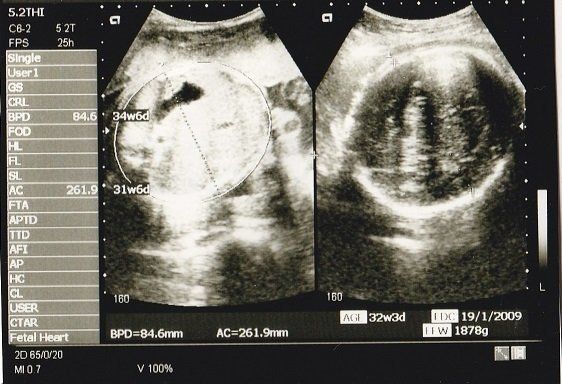

妊娠32週目のエコー写真 おなかもぱんぱんです。

AC(おなかの周囲の長さ)などから、赤ちゃんの推定体重を計算するようです。赤ちゃんのおなかも大きくなっていますが、お母さんのおなかもぱんぱんです。

妊娠35週目のエコー写真 いよいよ出産へ

妊娠9カ月になり、いよいよ出産に向けての準備段階です。母親学級に参加して、出産についていろいろと勉強しました。待望のわが子に会えるまで、あと少しです!

私の息子は生まれたときから髪がふさふさでした。このころから髪が伸びていたのかな?